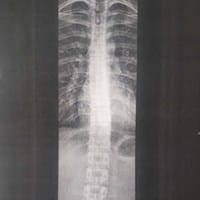

¿Cuantos grados de escoliosis tengo.? RX columna vertebral.

Me hice una radiografía de columna vertebral total. Pero no e conseguido que nadie me diga cuantos grados tengo de escoliosis. Unos me dicen que es de TIPO C y otros TIPO S pero en si no me dicen los grados. Me urge saber porque pienso presentarme a...